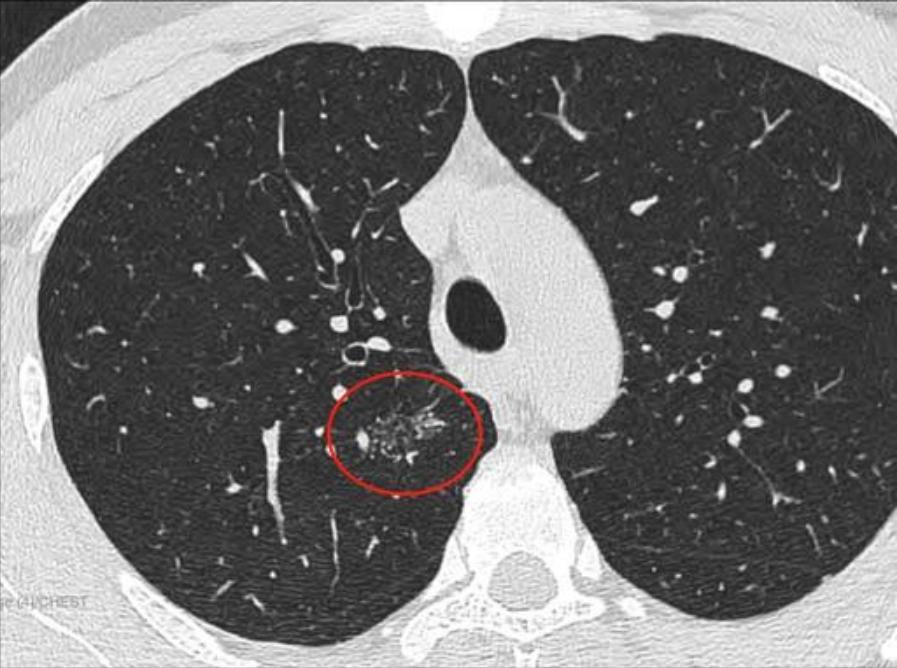

2022年7月29日去同一家A医院复查拍CT,检查结果如下,四个月后,结节从1.2变成了1.9 cm,发现结节长这么快,真的很慌,我老公不抽烟不喝酒,身体一直比较健康,没有住过院都,也没有家族史,不知道一下就长这么大一个结节,求助各位病友,各位医生,还有敬爱的戴主任,麻烦各位有经验的帮忙看看,我们目前只看上一个北京三甲医院普通号的大夫,大夫只说磨玻璃不应该长这么快,长的挺奇怪,不典型,其他没说什么,还没挂上其他医院的号,先麻烦各位帮忙看看,万分感谢!

CT截图: